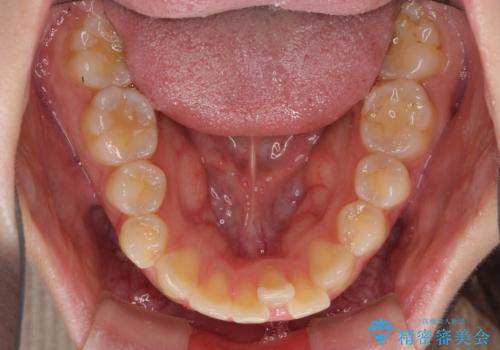

抜歯矯正の後戻り インビザラインによるオープンバイトの再矯正

- 以前矯正治療をされていましたが、後戻りが起きたことを気にして来院された患者様です。

上下前歯のオープンバイトを改善するため、インビザラインにて治療を行うこととしました。

外食が楽しみである患者様だったので、インビザラインによる治療期間は我慢の時期であったようです。

自己管理を徹底していただいたので、1年程度で治療を終えることができました。